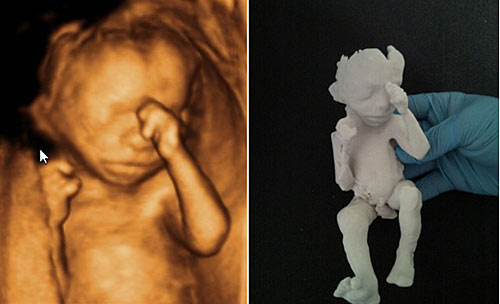

图:令准爸爸准妈妈惊呼的超逼真胎儿模型(3)

18周大的胎儿模型。